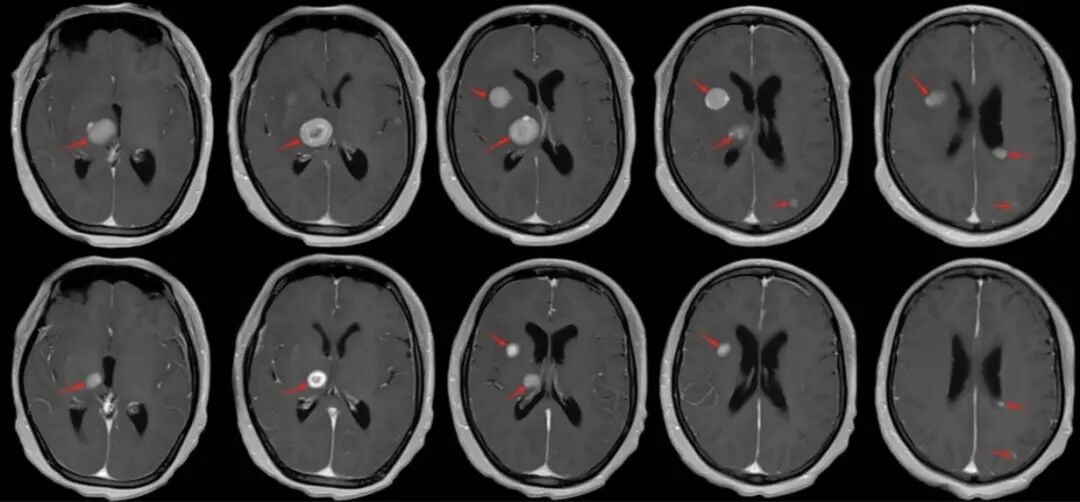

【學科風采】乳腺癌患者千里求醫(yī),成功治療多發(fā)腦轉移瘤、脊髓轉移、腦膜轉移、椎管內多發(fā)轉移結節(jié)、肺炎及肺門轉移患者